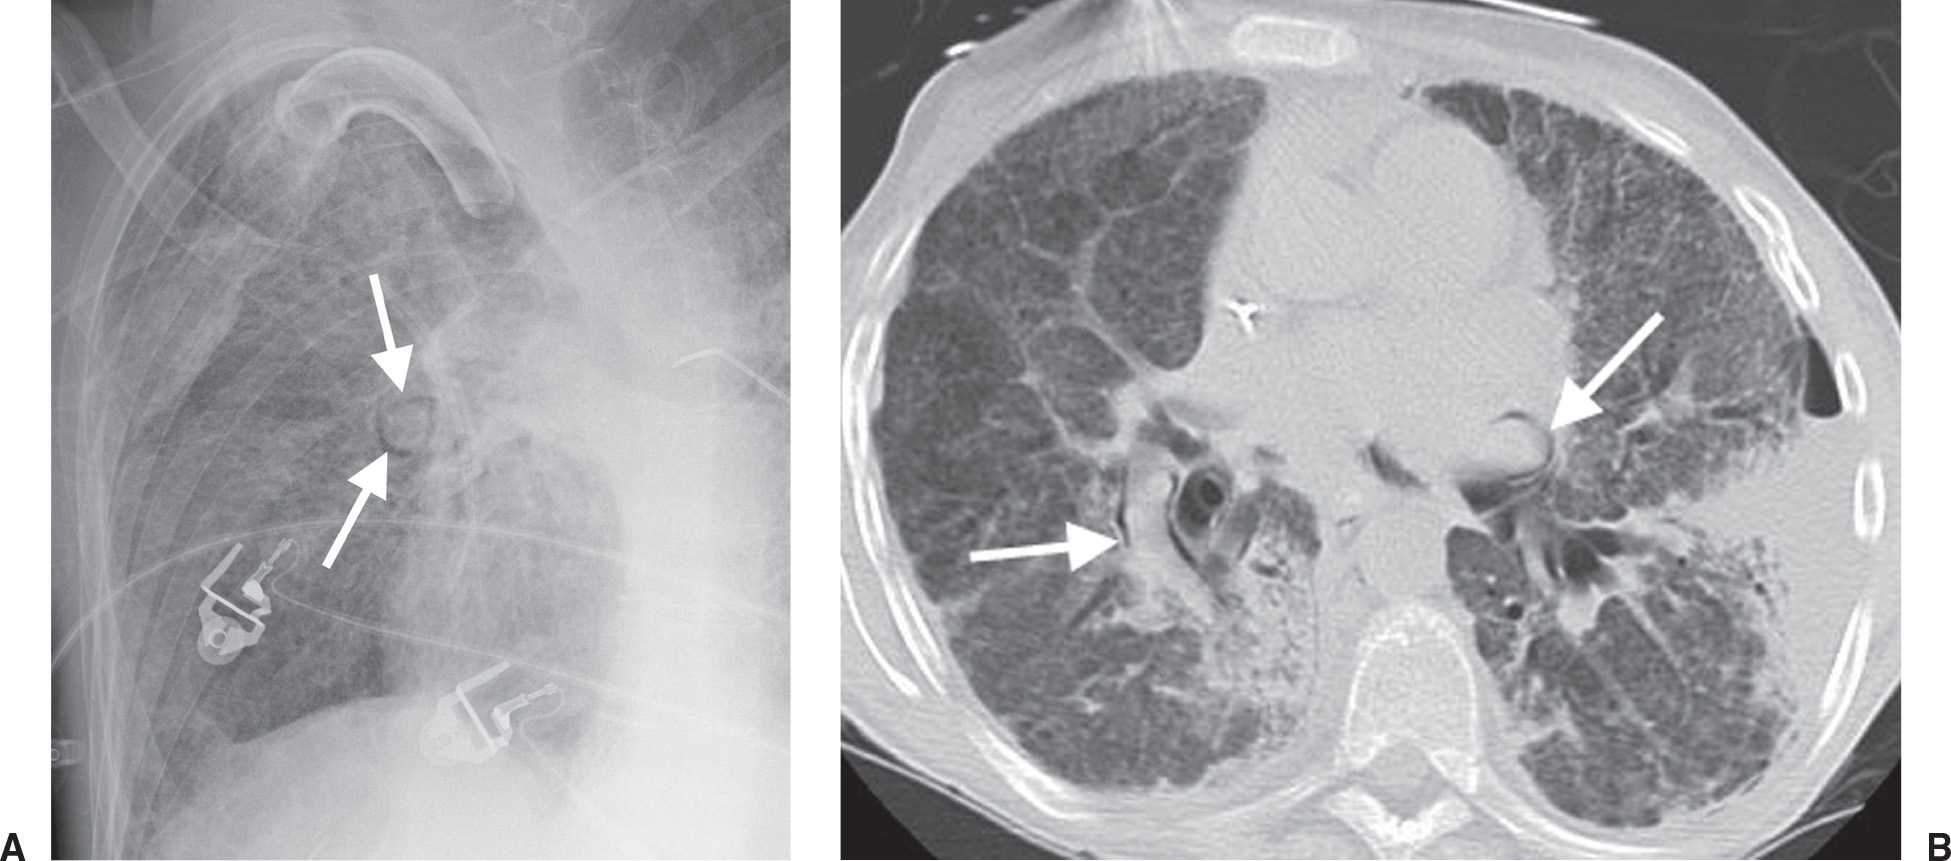

Chest radiology in intensive care Rings Around Lungs In this condition, part of the body's main artery or its branches form a ring around the windpipe,. Gas may originate from the lungs, trachea, central bronchi,. That means it's a congenital heart defect. Pneumomediastinum is the presence of extraluminal gas within the mediastinum. The signet ring sign is seen in bronchiectasis when the dilated bronchus and accompanying pulmonary artery. Rings Around Lungs.

Pneumothorax Causes, Signs, Symptoms, Treatment Rings Around Lungs Gas may originate from the lungs, trachea, central bronchi,. That means it's a congenital heart defect. Pneumomediastinum is the presence of extraluminal gas within the mediastinum. The signet ring sign is seen in bronchiectasis when the dilated bronchus and accompanying pulmonary artery branch are seen. In this condition, part of the body's main artery or its branches form a ring. Rings Around Lungs.

The Radiology Assistant Lung disease Rings Around Lungs That means it's a congenital heart defect. A vascular ring is a heart problem present at birth. Pneumomediastinum is the presence of extraluminal gas within the mediastinum. Pneumothorax in the supine position shows different. Gas may originate from the lungs, trachea, central bronchi,. Thoracic abnormal air collects in multiple thoracic spaces, including the pleural cavity, chest wall, mediastinum, pericardium, and. Rings Around Lungs.

Emerging roles for transthoracic ultrasonography in pleuropulmonary Rings Around Lungs Pneumothorax in the supine position shows different. In this condition, part of the body's main artery or its branches form a ring around the windpipe,. Type 2 is the most. That means it's a congenital heart defect. Thoracic abnormal air collects in multiple thoracic spaces, including the pleural cavity, chest wall, mediastinum, pericardium, and lung. Vascular rings are congenital vascular. Rings Around Lungs.